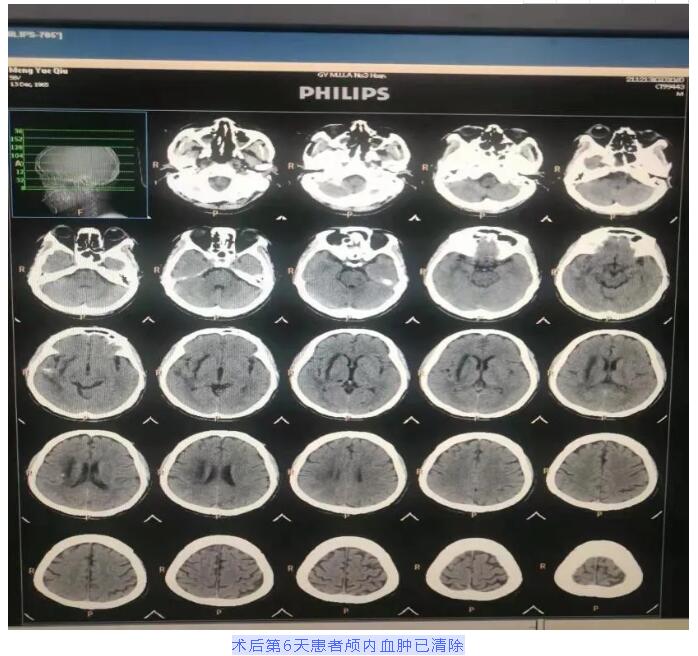

患者术后第4天拔除穿刺针,第6天复查头颅CT显示颅内血肿已清除。右侧肢体肌力5级,左侧肢体肌力4级。